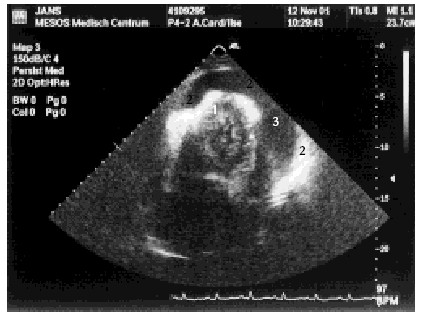

Harttamponnade, een levensbedreigende complicatie na een coronary bypass

Mevrouw Van Asten belt een beetje paniekerig op voor haar man. Hij is 2 weken geleden aan zijn hart geopereerd en is nu zo vreselijk moe. Ik ken de heer Van Asten, 63 jaar, als een wat bezorgde, precieze man. Hij heeft 2 weken geleden een coronary-bypass-operatie ondergaan wegens toenemende…